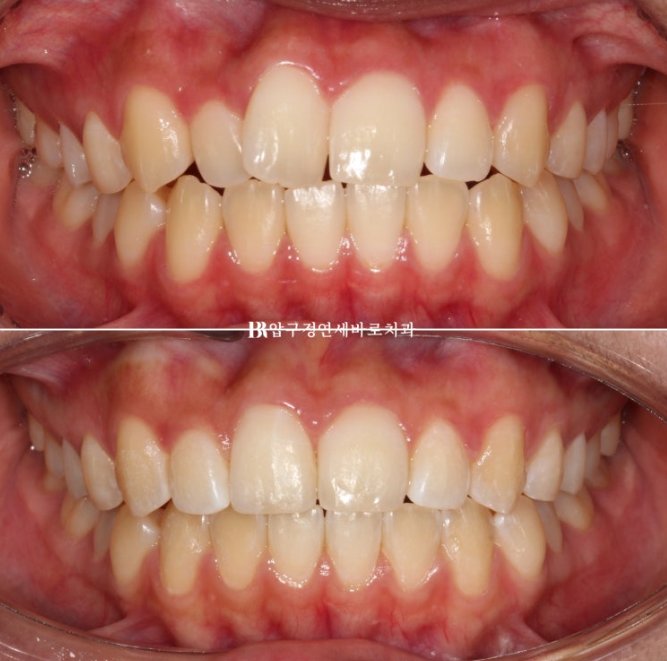

전 후 비교 보겠습니다.

토탈 치료 기간은 6개월 입니다.

23.12~24.06